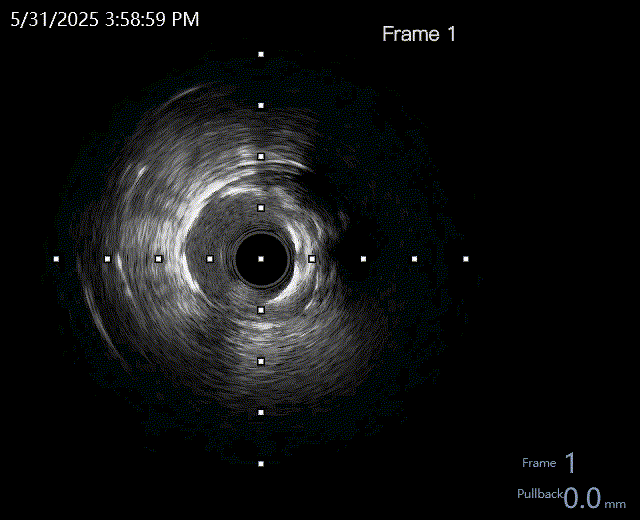

球囊预扩

选择不同尺寸的预扩球囊逐级预扩张病变,复查造影狭窄减轻不明显。为了解血管真实情况,遂启用IVUS检查。

术前腔内影像学IVUS指导

IVUS提示血管内钙化严重,最小管腔面积不足 4mm²;遂考虑启动IVL治疗。

冲击波球囊治疗

2.5*12mm@4atm 冠脉血管内冲击波导管反复进行8个周期治疗,经IVUS检查提示最小管腔面积增加至4.88mm²;随后选取后扩张球囊对病变行扩张治疗。

支架植入并后扩

于LM-LAD依次植入两枚药物洗脱支架,经非顺应性球囊后扩张支架,复查造影&IVUS提示血管内钙化仍较重,支架贴壁不良,遂再次启动IVL治疗。

再次冲击波球囊治疗

3.0*12mm@4atm 冠脉血管内冲击波导管反复进行5个周期治疗,并选取后扩张球囊对病变行扩张治疗。最终复查造影提示残余狭窄小于10%,未见夹层及血肿,TIMI血流3级。